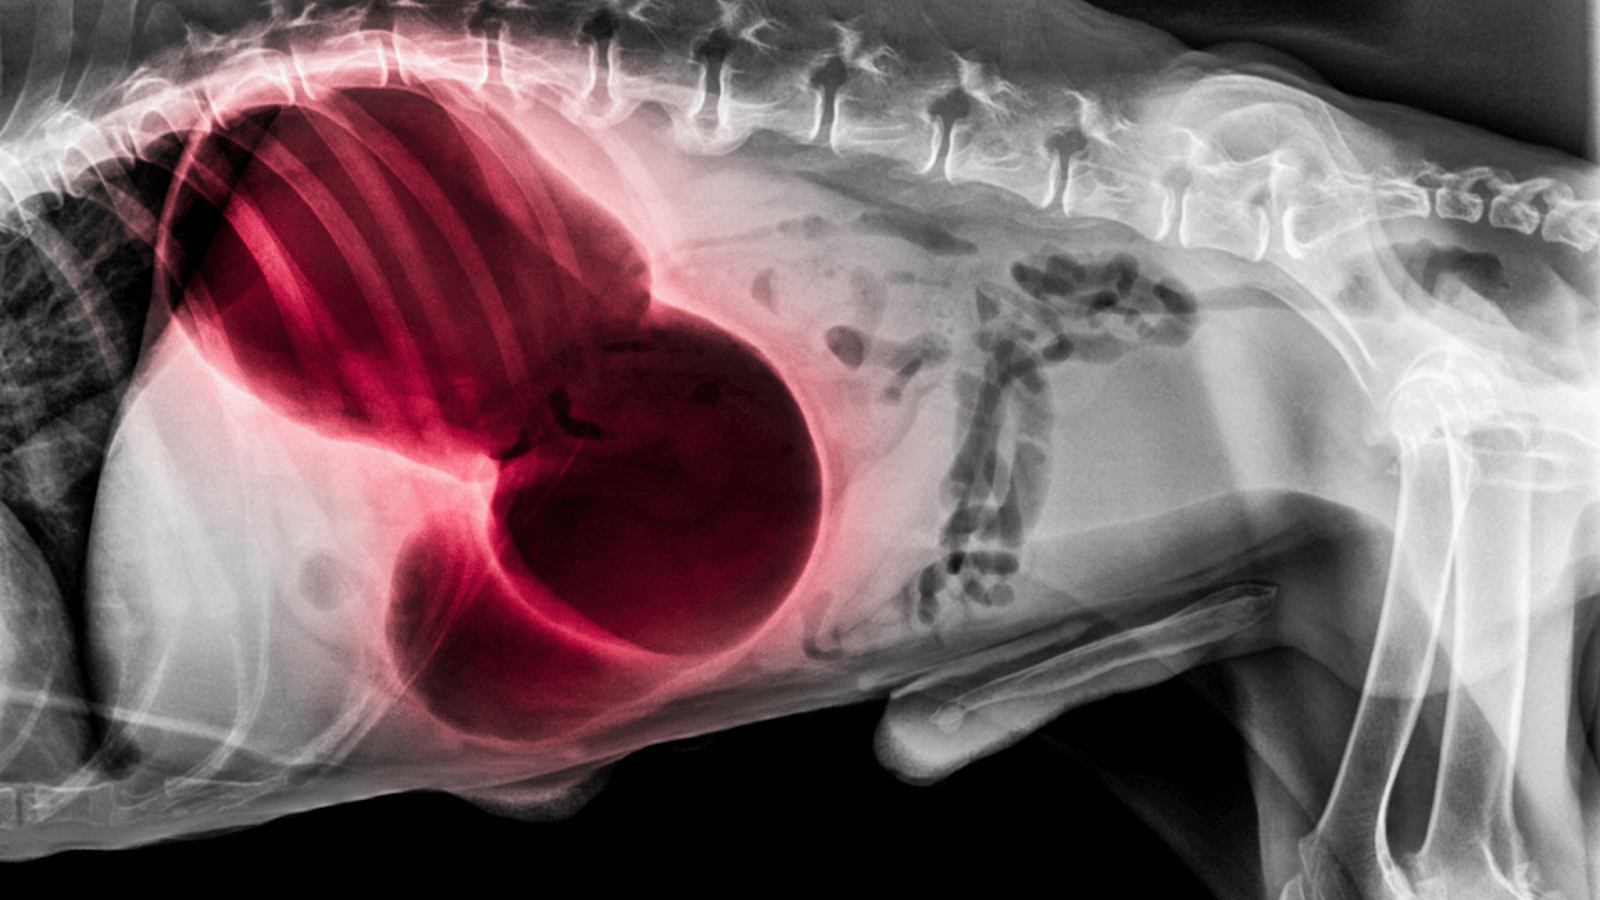

X-ray showing a dog's stomach to check causes of gurgling